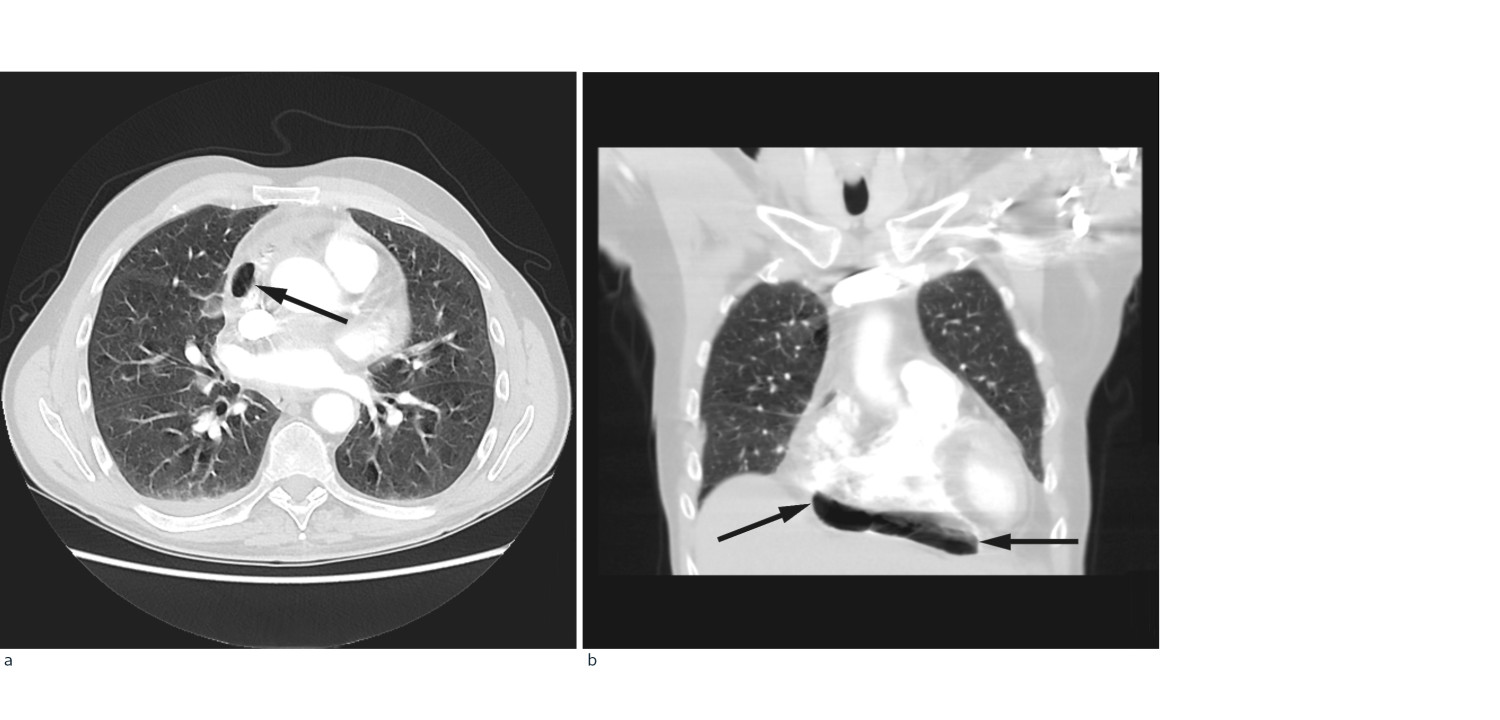

På mistanke om infeksjonsutvikling med utgangspunkt i lever/galleveier eller pancreas, ble intravenøs behandling med cefotaxim 1 g x 4 startet. Ultralyd abdomen viste slanke galleveier, men radiolog anbefalte CT abdomen for endelig avklaring. Dette ble utført samme dag supplert med CT thorax med lungeemboliserie. Underveis i denne undersøkelsen fikk pasienten akutt økende dyspné med metningsfall til 70 %, takypné med respirasjonsfrekvens på 22/minutt og takykardi med puls på 130 slag/minutt, ledsaget av kraftig forverring av smertene i høyre hemithorax. Onkolog og anestesilege ble tilkalt. Med ventilasjonsstøtte på maske klarte pasienten å gjennomføre undersøkelsen som viste fri luft i mediastinum, hovedsakelig i perikard, samt noe perikardeffusjon (fig 1). Lekkasjestedet kunne ikke påvises. I buken var det ingen fri luft.

I foreliggende pasienthistorie var det spredning av både kreftceller og bakterier til epi- og perikard. Ved obduksjonen ble det ikke påvist økt luft/gass i perikard. Dette kan likevel ikke utelukkes, da man ikke spesifikt undersøkte for dette. Fistel mellom perikard/mediastinum og øvre gastrointestinalkanal eller trachea ble heller ikke avdekket, skjønt en liten åpning kan heller ikke utelukkes. På CT-undersøkelsen tatt dagen før dødsfallet er luft godt synlig (fig 1), men det var ikke mulig å identifisere lekkasjestedet. Sannsynligvis har maligne celler erodert perikard og epikard fra mediastinum, som ledd i det infiltrative vekstmønsteret, hvilket kan ha skapt en ventil for bakterier og luft. Fri luft/gass kunne også tenkes å ha oppstått som et (bi-)produkt av en bakteriell superinfeksjon med autolyse og vekselvirkning mellom bakterielt toksin og karsinomceller. Infeksjoner med gassproduserende bakterier i tarm eller bløtvev gir imidlertid som regel kun små gasslokulamenter på CT. Mikrobene som ble påvist er heller ikke typisk gassproduserende. Pasienten hadde ikke gjennomgått invasive prosedyrer utover biopsitakning fra lymfeknuter i øvre mediastinum, som ble utført tre uker tidligere. Denne prosedyren er rapportert å kunne forårsake penumomediastinum, men da som en akutt komplikasjon (5). Bruk av steroider og antibiotika i kombinasjon kunne potensielt forårsaket kolonisering eller infeksjon av sopp i oesophagus, med påfølgende ruptur. Det ble derimot ikke sett tegn til dette under obduksjonen. Pneumomediastinum kan utløses av kraftige hosteanfall, uten at en slik rift i luftveiene er synlig på CT. Iomeron, kontrastmidlet som gis i forbindelse med CT, kan utløse hoste, men dette er ikke journalført som et fremtredende symptom hos denne pasienten.